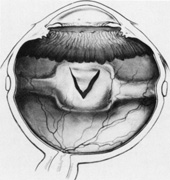

A helpful intraoperative sign to determine the adequacy of subretinal fluid drainage is to assess the contour of the retina in relation to the scleral buckle. If after drainage the retina follows the contour of the buckle, drainage is usually adequate even if there are residual subretinal fluid and retinal folds. However, if after drainage and elevation of the buckle the retina does not appear to follow the contour of the buckle or if the buckling effect is not visible beneath the retina, additional drainage usually is necessary (Fig. 33).

Fig. 33. A. Retinal tear elevated after drainage and placement of a scleral buckle. B. Retinal tear partially closed after drainage with the retina conforming to the shape of the buckle.